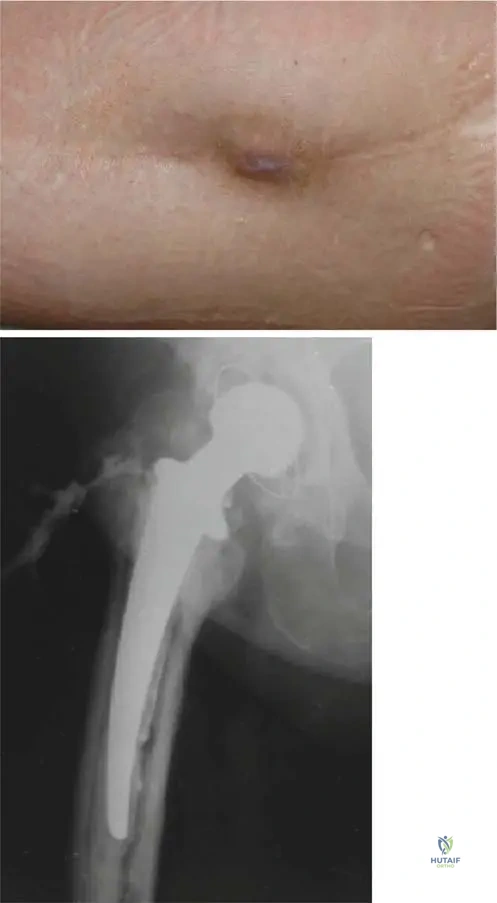

A 52-year-old male with a 20-year history of heavy alcohol consumption presents with severe right hip pain, significantly limiting his ambulation. He reports progressive pain over the past year. Physical examination shows a Trendelenburg gait, markedly restricted and painful range of motion in all planes of the right hip. Radiographs reveal flattening and sclerosis of the right femoral head with subchondral collapse and joint space narrowing.

View Answer & Explanation

Correct Answer: C

Rationale: The radiographic findings of femoral head collapse (subchondral collapse) and joint space narrowing in the setting of avascular necrosis (AVN) indicate advanced disease (e.g., Ficat Stage III or IV). At this stage, joint-preserving procedures like core decompression or osteotomy are generally not effective. Total hip arthroplasty is the most appropriate surgical treatment for advanced AVN with femoral head collapse and significant functional impairment. NSAIDs and activity modification are palliative and insufficient for advanced disease. Arthrodesis is rarely performed for hip AVN due to its significant functional limitations.